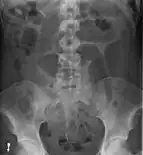

Diagnosis

After taking a thorough history, the diagnosis of colonic volvulus is usually easily included in the differential diagnosis. Abdominal plain x-rays are commonly confirmatory for a volvulus, especially if a "bent inner tube" sign or a "coffee bean" sign are seen. These refer to the shape of the air-filled closed loop of colon which forms the volvulus. Should the diagnosis be in doubt, a barium enema may be used to demonstrate a "bird's beak" at the point where the segment of proximal bowel and distal bowel rotate to form the volvulus.

This area shows an acute and sharp tapering and looks like a bird's beak. If a perforation is suspected, barium should not be used due to its potentially lethal effects when distributed throughout the free intraperitoneal cavity. Gastrografin, which is safer, can be substituted for barium.